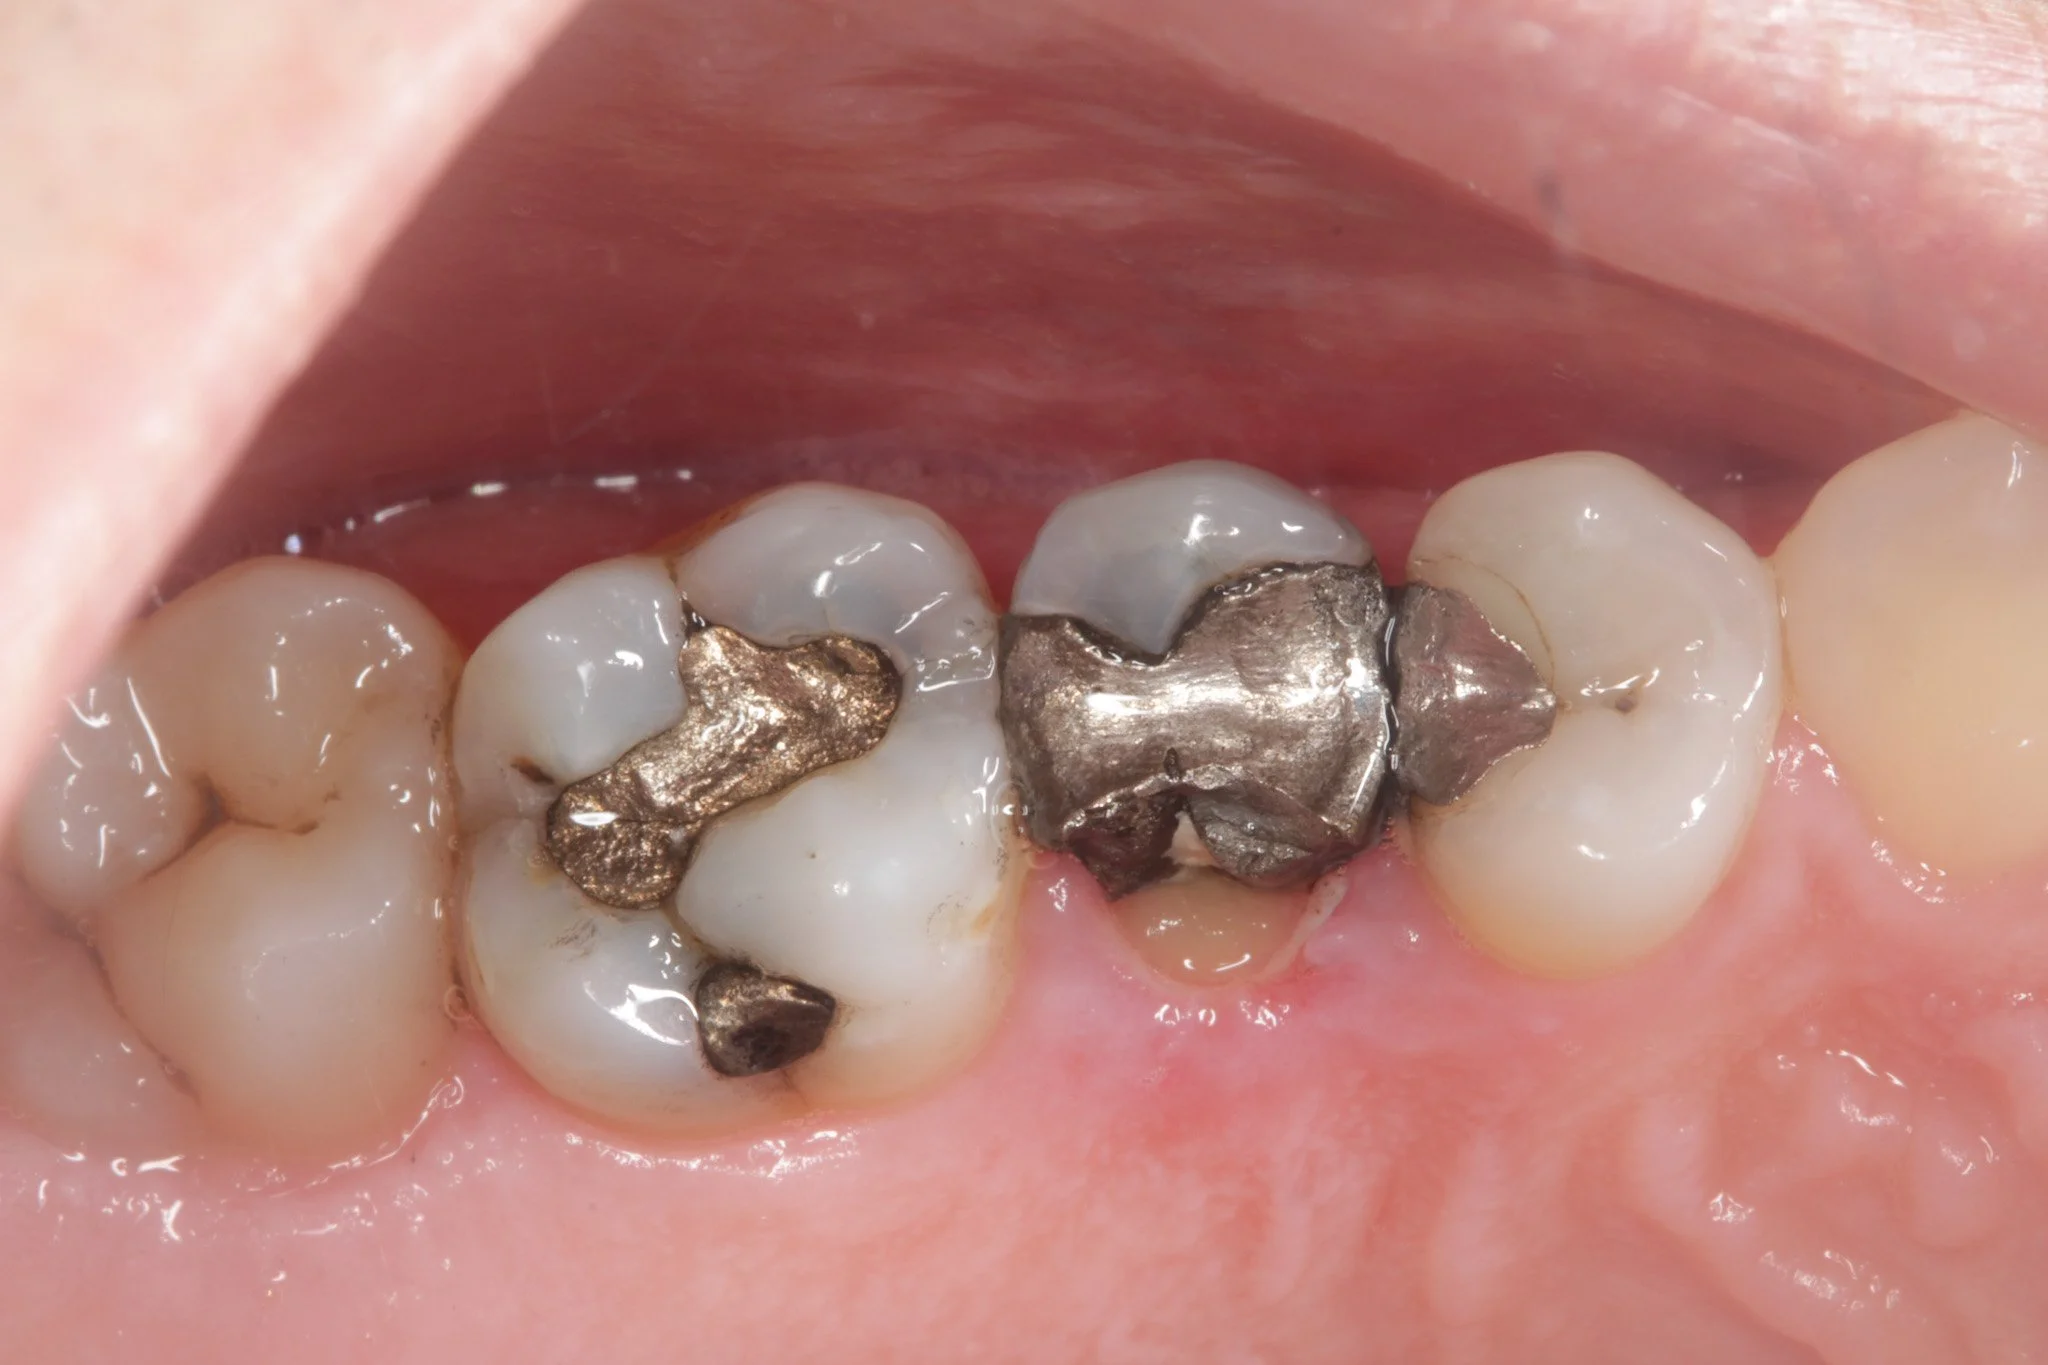

A deep metal dental filling